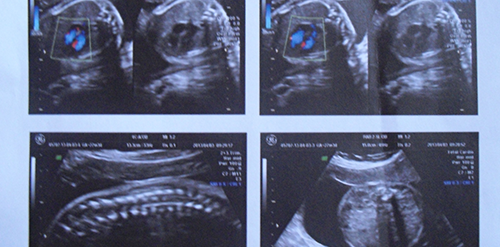

四维彩超是产检项目中非常重要的一项,此项检查能直观的看见腹中胎儿孕囊、胎头、胎心、脐带、羊水以及胎盘的情况,其目的是为了判断胎儿在生长发育中是否出现异常情况,而通过四维彩超的检查,确实是能够预知胎儿性别的。

四维彩超能清晰的看到胎儿的五官,通过这些能判断胎儿是否先天畸形。但这项检查也能观察到胎儿的性器官,因此就能通过胎儿的性器官预知宝宝的性别。

四维彩超也叫四维B超,它是B超的一种,所以b超也是能看胎儿性别的。那么b超怎么看胎儿性别?其实方法和四维彩超一样,b超检查也能看到胎儿的性器官,从而预知胎儿性别。